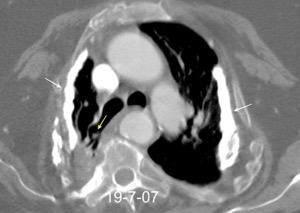

Síndrome de afectación postcardiaca (postcardiac injury)

Post infarto 1-7 % (Dressler)

Trauma cerrado Implantación marcapasos

Cirugía cardiaca. 17-31% (Post.pericardiotomía)

3707 pacientes 29 Derrames (0,78%) > de 25% del hemitórax

Todas menos 2 Izdos.

Angioplastia

By-pass coronario 21-10-03